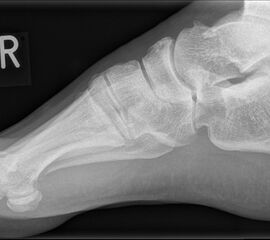

Abbildung 1: Plantarer und dorsaler Sporn im Röntgenbild und im MRT

Abb. 1a und Abb. 1b: großer dorsaler Fersensporn und ein minimaler plantarer Sporn, Patient, 50 Jahre.

Abb. 1c: Bild eines isolierten großen plantaren Fersensporns. Patientin, 32 Jahre.

Dorsaler Fersensporn: Dorsale Fersenschmerzen können auch durch einen echten dorsalen Fersensporn entstehen (siehe Abb. 1). Dieser entsteht als knöcherne Ausziehung durch Verkalkung der Achillessehne an ihrem Ansatz.